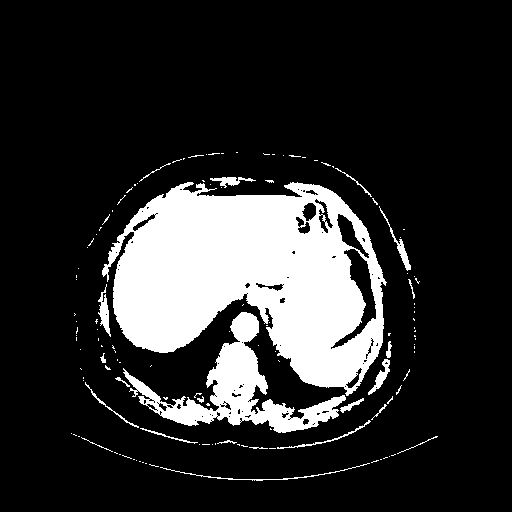

Original VENOUS CT scan

Full window (WL 1023.5, WW 4095 β†’ Low βˆ’1024, High +3071)

Actual HU range: [-1024.0, 3071.0]